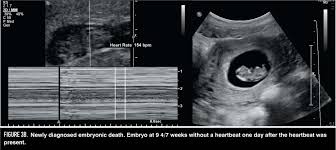

How Long Can An Anembryonic Pregnancy Last - ≥11 days after scan showing gestational sac with yolk sac, but no embryo, or 1.2.. In an anembryonic pregnancy or blighted ovum pregnancy, the sac develops, however, there is no foetus inside. Interestingly, a recent study found significantly fewer trophoblasts in women who had been diagnosed with ectopic pregnancy (an embryo attached outside the uterus) or blighted ovum. In anembryonic pregnancy, a blastocyst is formed from a fertilised ovum, but the fetal pole/embryonever develops, though histologically some fetal material can be demonstrated in most cases. Absent yolk sac when msd >8 mm on transvaginal ultrasound (tvus) 2. The patient may be asymptomatic, presenting for an early pregnancy ultrasound.

Mar 01, 2018 · natural expulsion may take up to two weeks. A blighted ovum eventually results in miscarriage. An ultrasound will show an empty gestational sac. A blighted ovum will cause a miscarriage usually at 7 to 12 weeks of pregnancy. May 19, 2020 · about 15 percent of all pregnancies end in miscarriage before 13 weeks of pregnancy. In an anembryonic pregnancy, however, the trophoblast attaches itself to the uterus, but the blastocyst never fully forms. Due to falling hcg levels, the clinical signs of pregnancy tend to subside. When there is no embryo seen on endovaginal scanning in a gestational sac with mean sac diameter (msd) ≥25 mm 4 or 1.